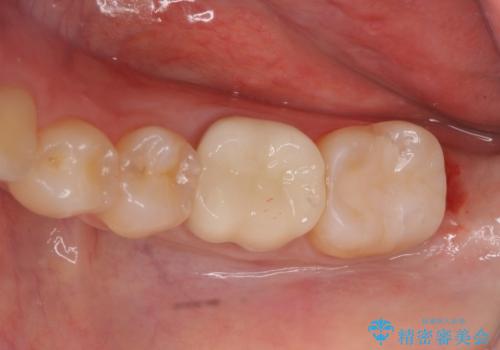

[フルジルコニアクラウン] 老朽化した銀歯を白く

![[フルジルコニアクラウン] 老朽化した銀歯を白くの症例 治療後](https://seimitsushinbi.jp/wp/wp-content/uploads/2020/05/60951366446f010978e24aba6c35e27e-500x350.jpg?v=1588518777)